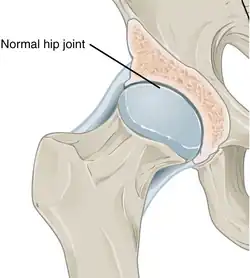

In a healthy joint, the ends of bones are encased in smooth cartilage. Together, they are protected by a joint capsule lined with a synovial membrane that produces synovial fluid. The capsule and fluid protect the cartilage, muscles, and connective tissues. -